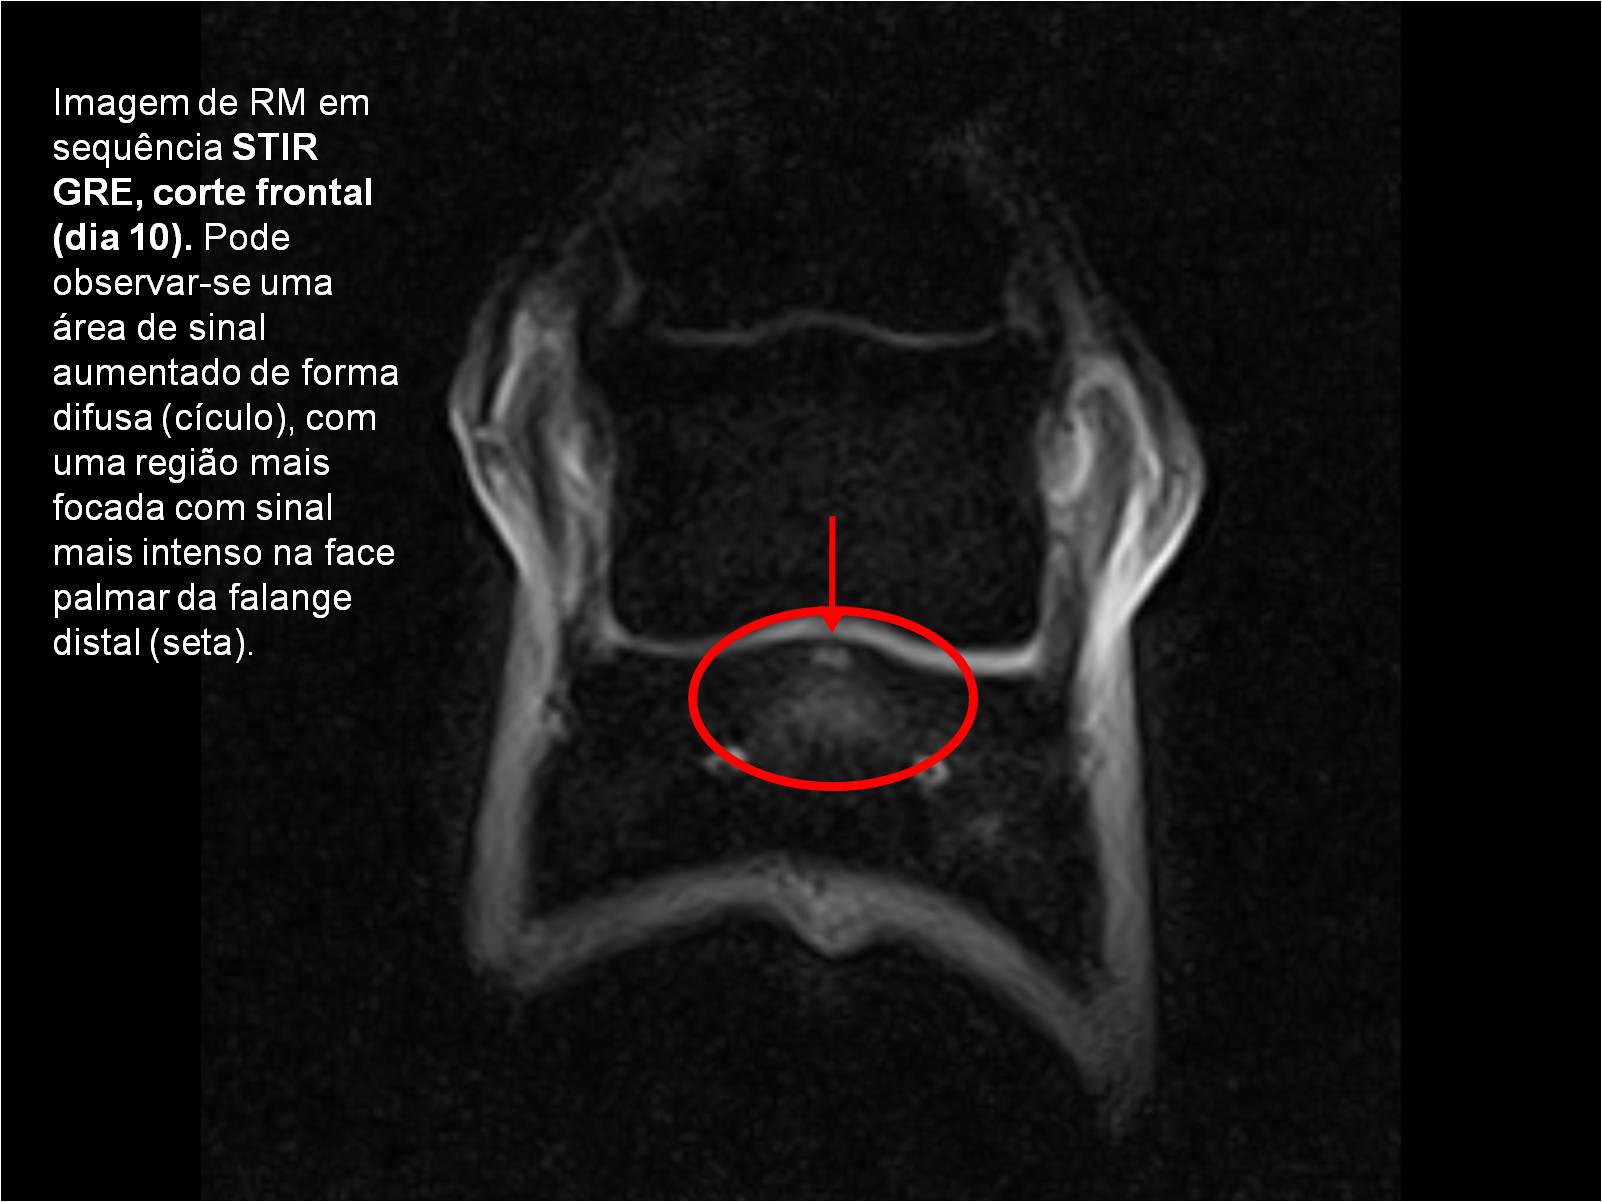

Publisher: Universidade de Évora

Abstract: O relatório de estágio encontra-se estruturado em três partes distintas. A primeira parte faz a caracterização das infraestruturas e funcionamento do Hospital Veterinário de Equinos de Lüsche, Oldenburg, Alemanha, assim como a análise casuística dos casos clínicos acompanhados durante os 6 meses de estágio. A segunda parte consiste de uma revisão bibliográfica sobre quistos do osso subcondral em equinos. Por fim, a terceira parte consta da apresentação e discussão de um caso clínico, nomeadamente o diagnóstico e acompanhamento imagiológico, por ressonância magnética, de um quisto subcondral na terceira falange num cavalo adulto; ### Abstract Equine Practice- Subcondral bone cyst of the third phalanx This internship report is divided in three parts. The first part characterizes the infrastructure and function of the Equine Hospital Lüsche, Oldenburg, Germany, as well as the casuistic of the clinical cases accompanied during the 6 month internship. The second part consists in a bibliographic review of cystic lesions of the subchondral bone in equines. The third part consists in a case report, the diagnostic and imagiological accompaniment, by use of magnetic resonance imaging, of a subchondral bone cyst in the distal phalanx of an adult equine.